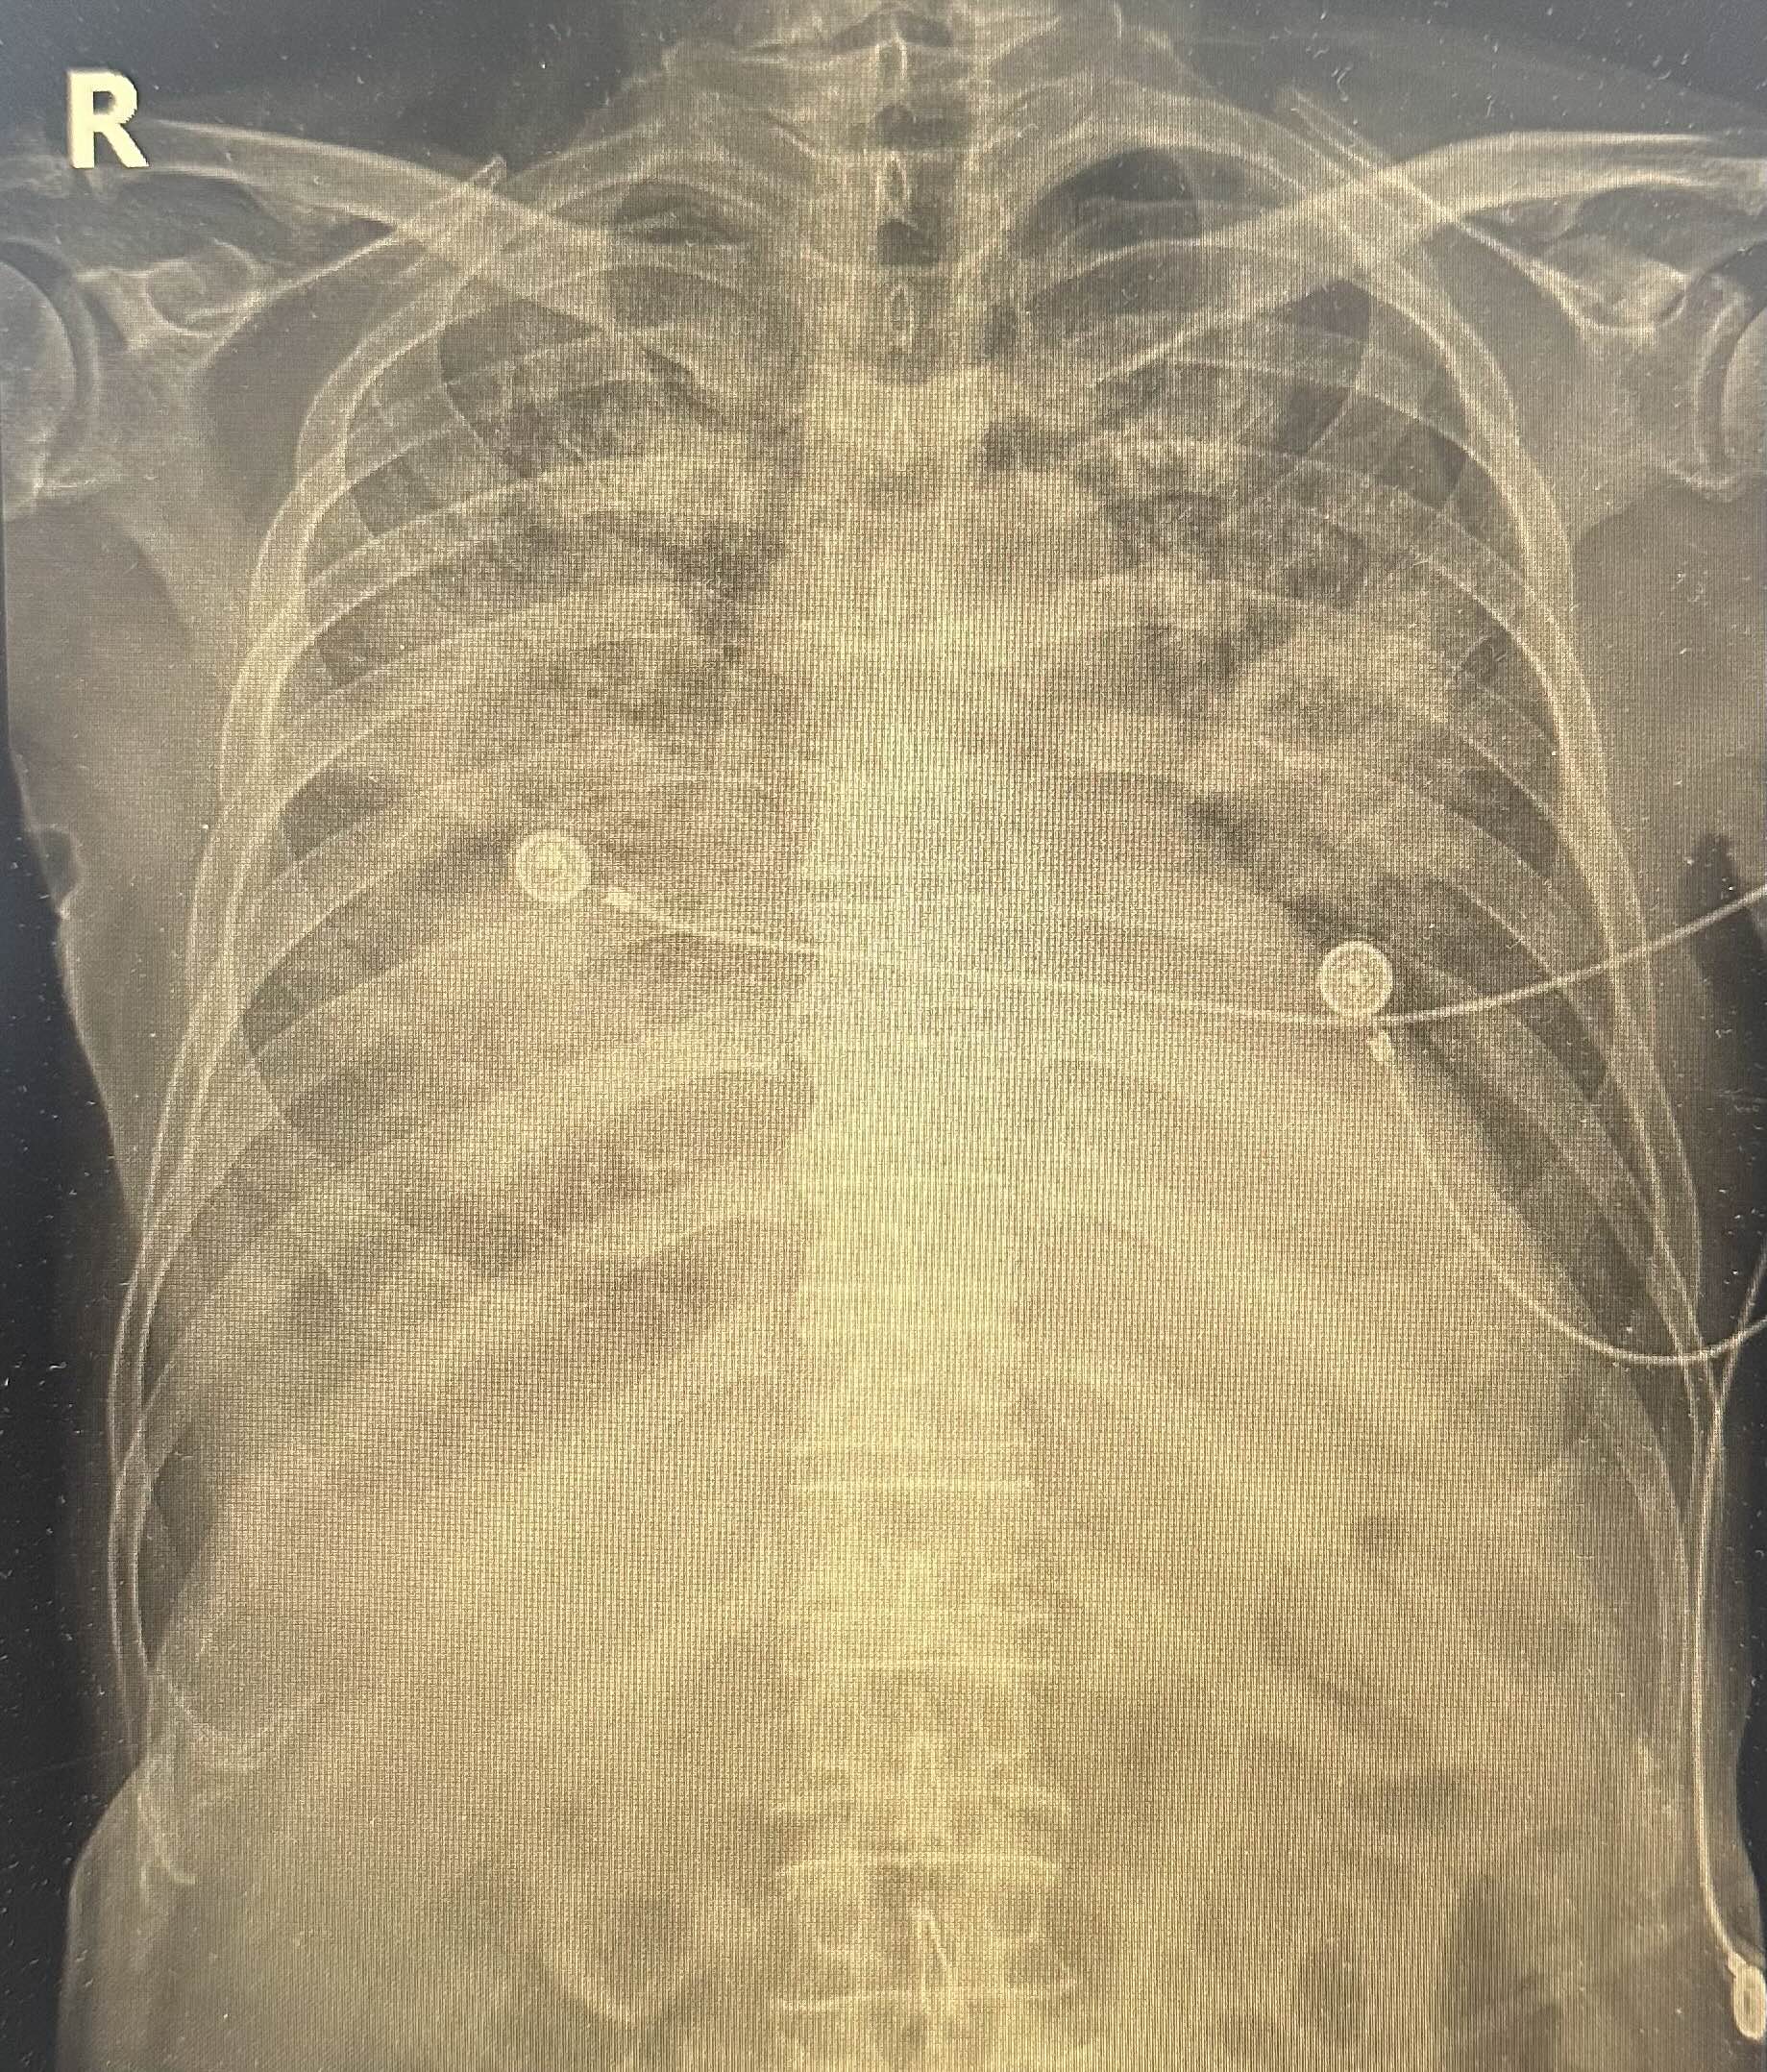

폐렴으로 입원치료를 한지 나흘째.. 호흡도 폐렴은 점차 심해져 급성 호흡곤란 증후군(ARDS)*과 같은 양상으로 나빠지고 있던 상태였다.

다만, 젊은 사람의 경우와는 달리 환자분의 지병과 폐렴의 기전(이환자의 경우엔 흡인성폐렴) 및 현재 x ray 등을 고려했을 때 호전되어 extubation을 하는 것은 쉽지 않아 보이며, 추후엔 기관절개술(tracheostomy)이 필요할 가능성이 높다는 설명을 드렸다.